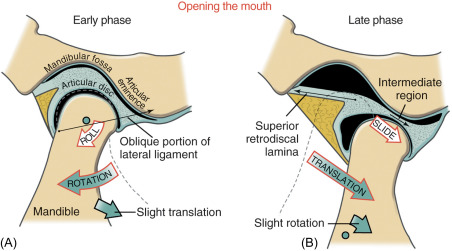

JAW movement

- 旋轉: 下顎離上門牙2.5cm

- 平移: disc-condyle complex 沿 articular eminence 滑動,可再往前張開約 1.5 公分

Join capsule

Articular eminence 到 articular fossa

Joint disk

-

分成 Ant. band(2mm), Central intermediate zone(1mm),

Post. band(3mm) -

Dense fiber CT,無神經血管

-

Lower division 連到 condylar neck 的 lat.,med. poles

-

Upper division 連到 Temporal bone 的 postglenoid process

collateral ligament

retrodiskal tissues

有神經血管,分秘 Synovial fluid 到 Synovial cavity

- Superior retrodiskal lamina:elastic fibers,接到 tympanic plate,限制平行移動

- Inferior retrodiskal lamina:Collagen fibers,將 disc 接到 condyle,限制旋轉移動

Ligament

- Temporomandibular ligaments

- Inner horizontal protion

限制向後 - Outer horizontal protion

限制旋轉、平移

- Inner horizontal protion

- Stylomandibular ligaments

- Sphenomandibular ligaments